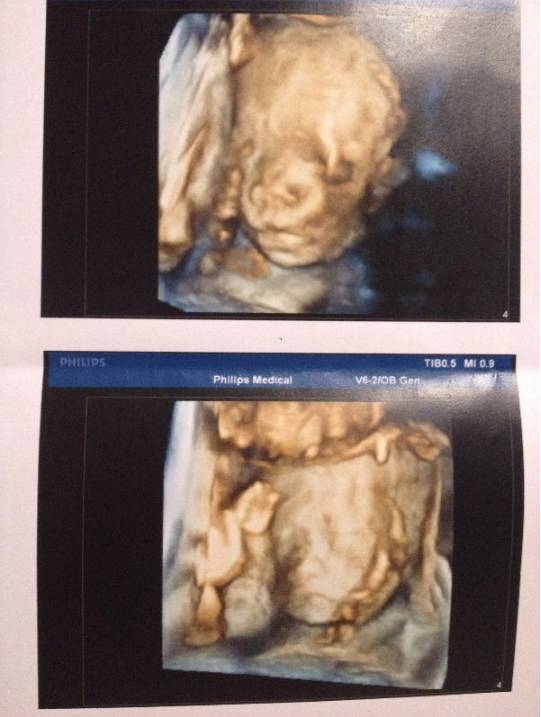

4月30日,29周+2天,第二次系统筛查也顺利通过。宝贝们的发育都很好,而且月龄还是只相差一周,体重差距也不大。四维照片大致能看出来宝贝的面部轮廓,都是比较秀气的宝宝,后面看到宝贝的时候得到了验证,尤其是左左的小脸,和四维照片中的相似度有90%。